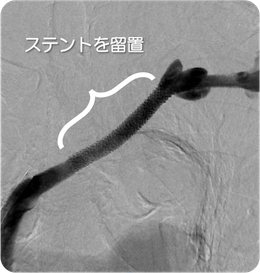

治療後

血管造影

左腸骨動脈が完全閉塞しており、左下肢の冷感、痛みを認めました。ステントを留置しいずれの症状も消失しています。